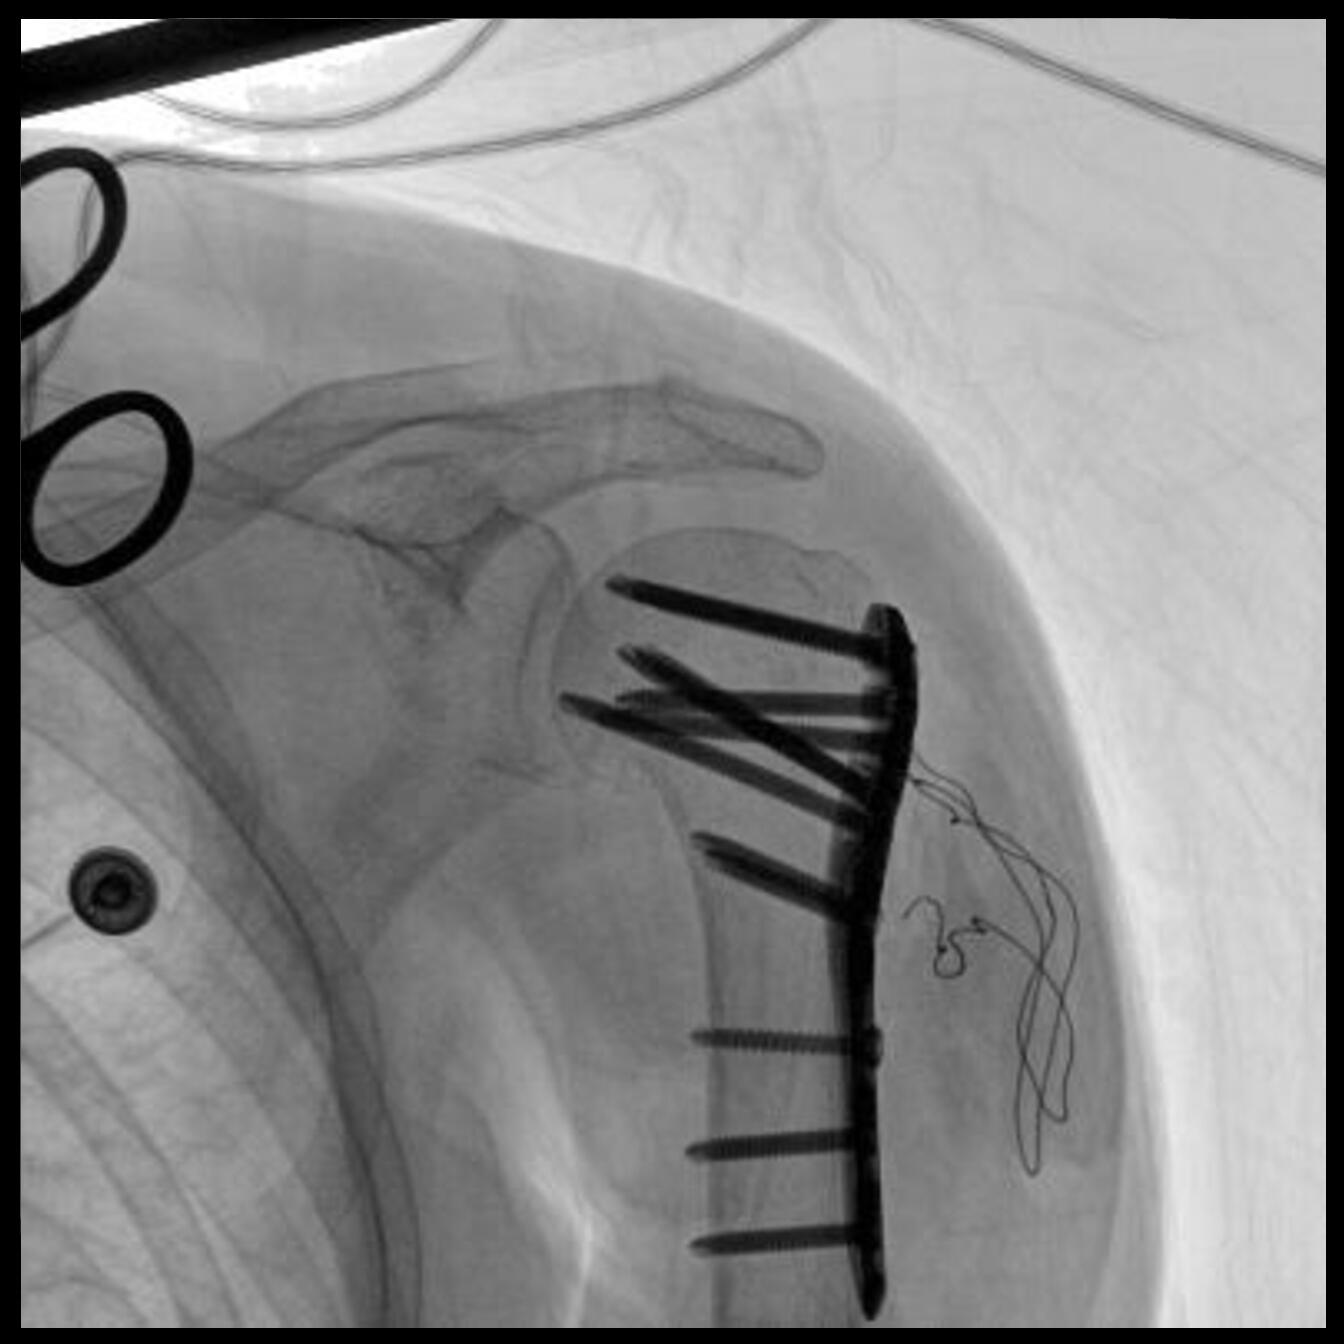

配備了兩種平板尺寸,大尺寸動(dòng)態(tài)平板探測(cè)器成像面積較傳統(tǒng)平板探測(cè)器提升了25%以上,在視野需求大的手術(shù)中,便于醫(yī)生更好定位病灶點(diǎn),規(guī)劃手術(shù)方案,減少因視野范圍不足而多次透視、點(diǎn)片造成的不便。

Clinical picture

臨床圖片